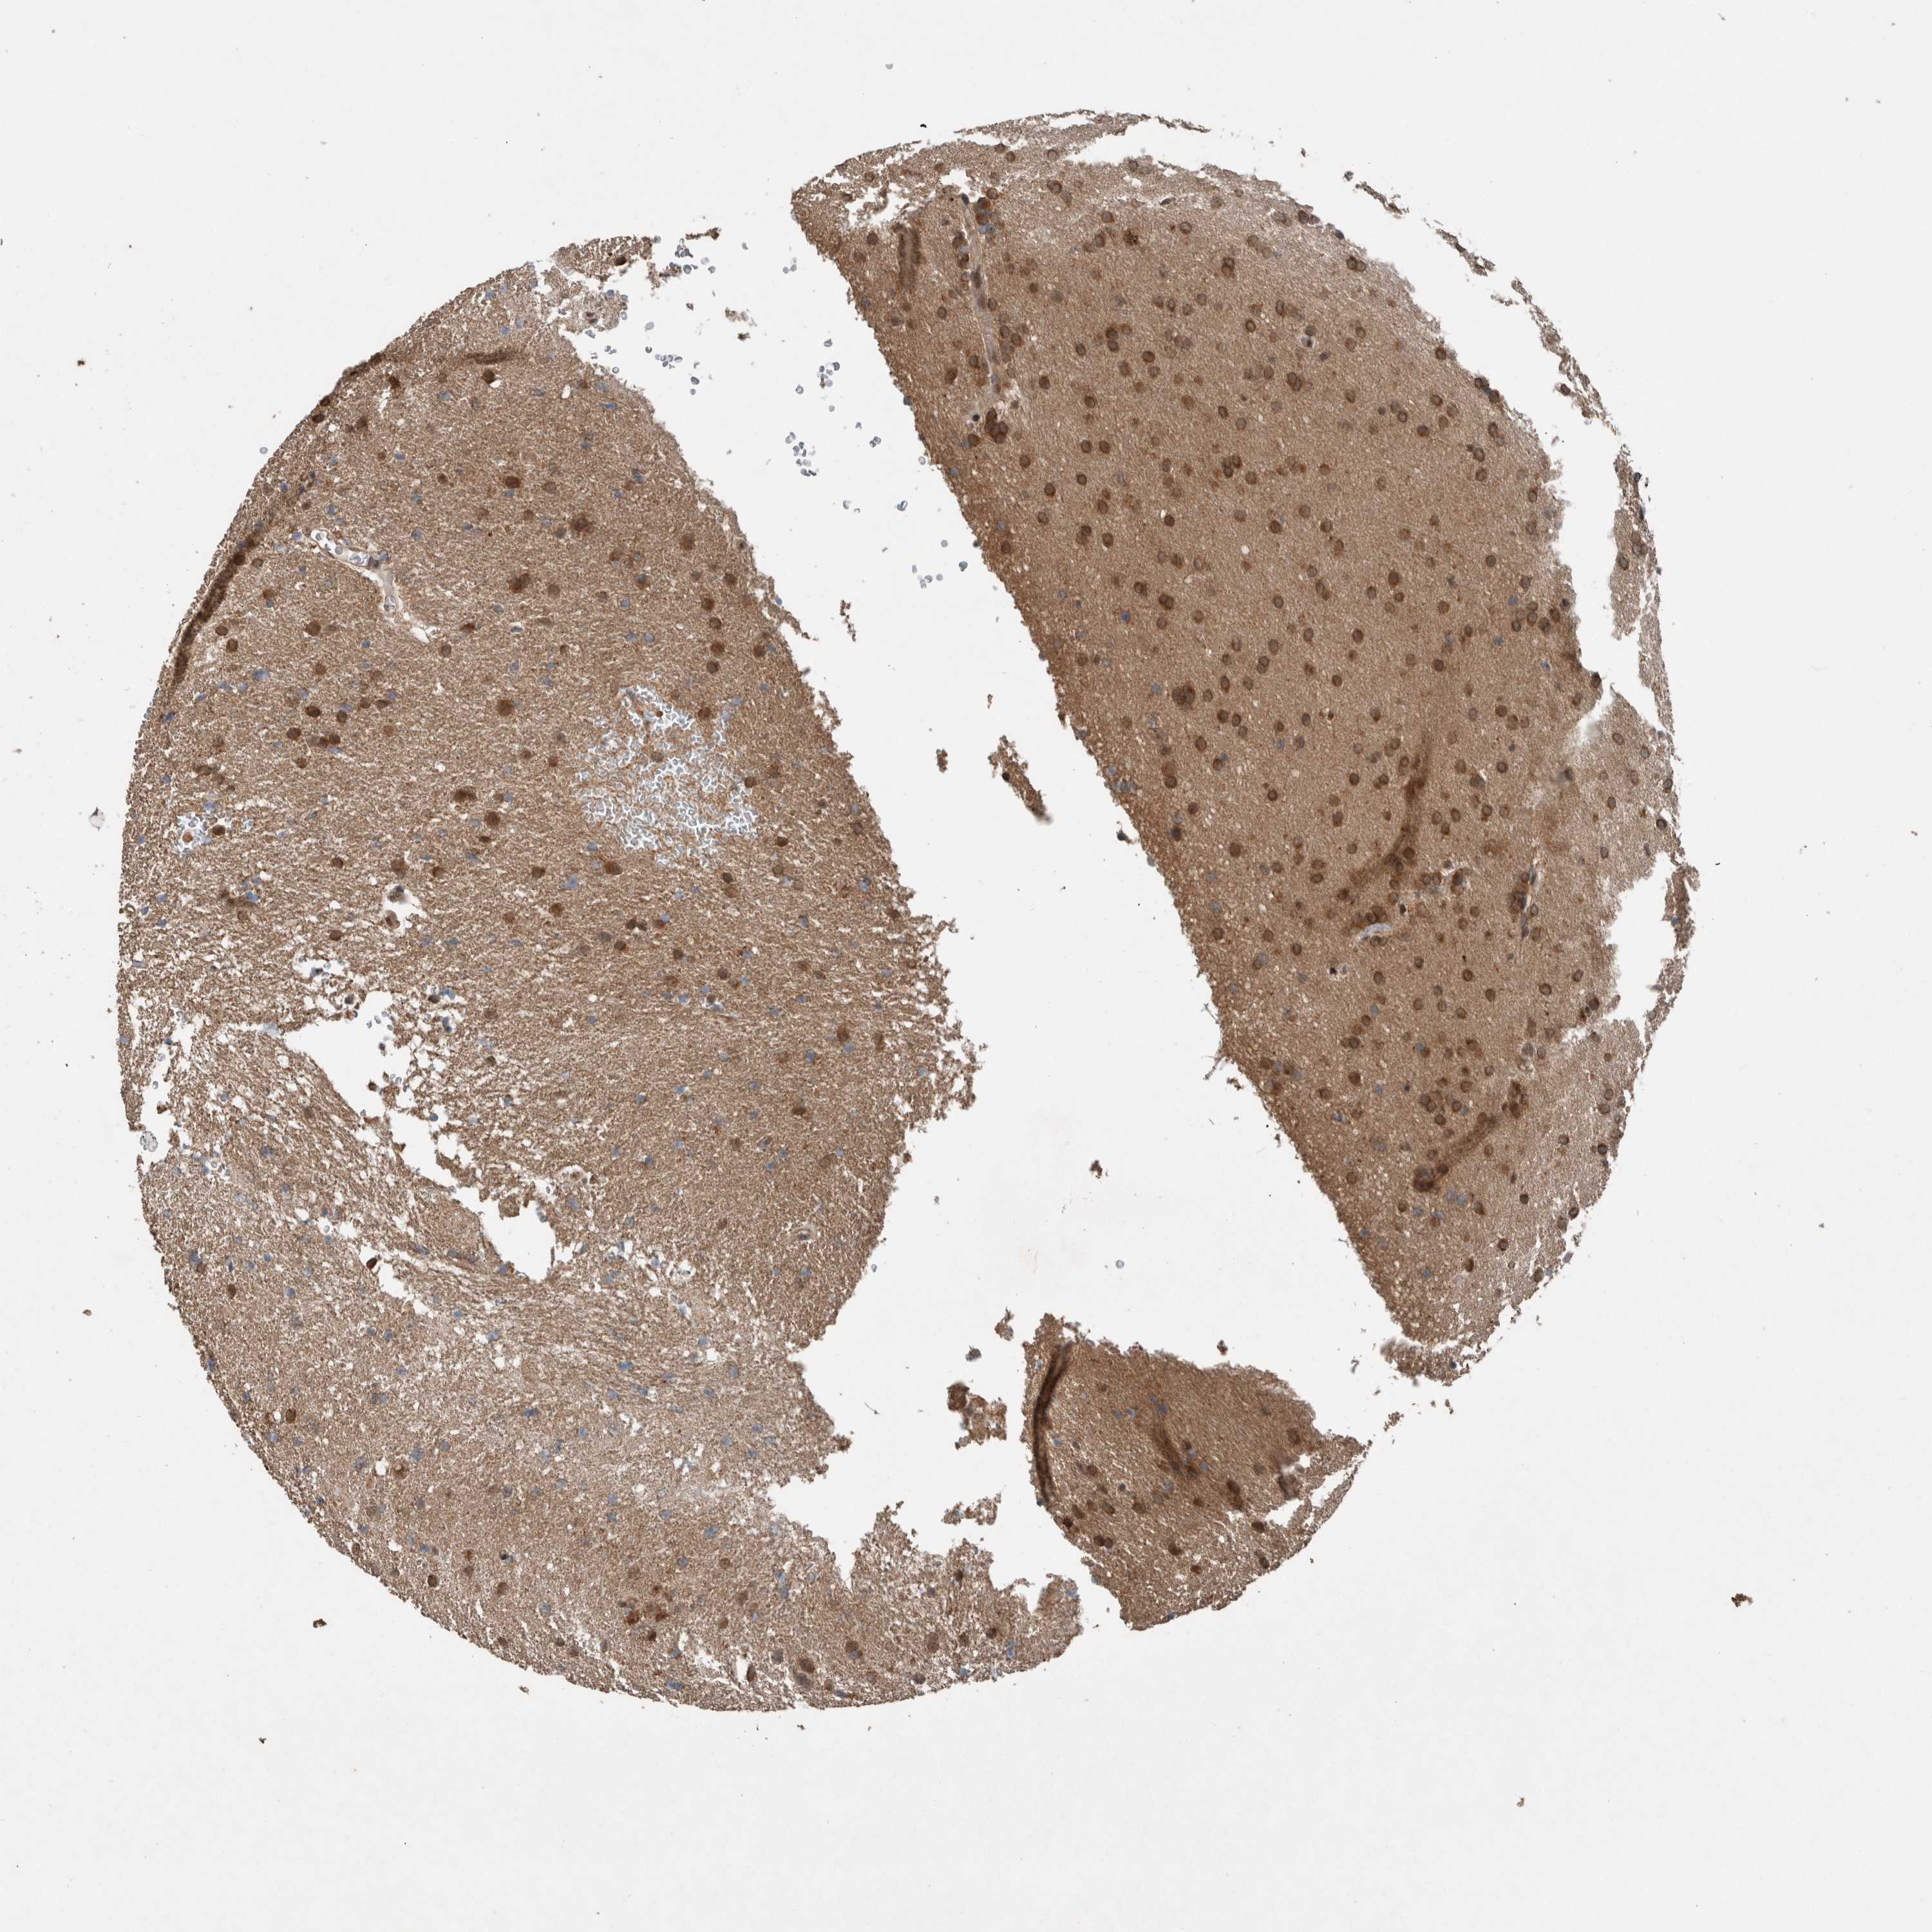

GLIOMA - Protein expressioni

A mouse-over function shows sample information and annotation data. Click on an image to view it in a full screen mode. Samples can be filtered based on level of antibody staining by selecting one or several of the following categories: high, medium, low and not detected. The assay and annotation is described here.

Note that samples used for immunohistochemistry by the Human Protein Atlas do not correspond to samples in the TCGA dataset.

Antibody stainingi

Antibody staining in the annotated cell types in the current human tissue is reported as not detected, low, medium, or high, based on conventional immunohistochemistry profiling in selected tissues. This score is based on the combination of the staining intensity and fraction of stained cells.

Each image is clickable and will lead to virtual microscopy that enables deeper exploration of all samples and also displays staining intensity scores, fraction scores and subcellular localization as well as patient and tissue information for each sample.

Antibody HPA023886

Staining

High

Medium

Low

Not detected

Intensity

Strong

Moderate

Weak

Negative

Quantity

>75%

75%-25%

<25%

None

Location

Nuclear

Cytoplasmic/membranous

Cytoplasmic/membranous,nuclear

Glioma, malignant, High grade

Glioma, malignant, Low grade